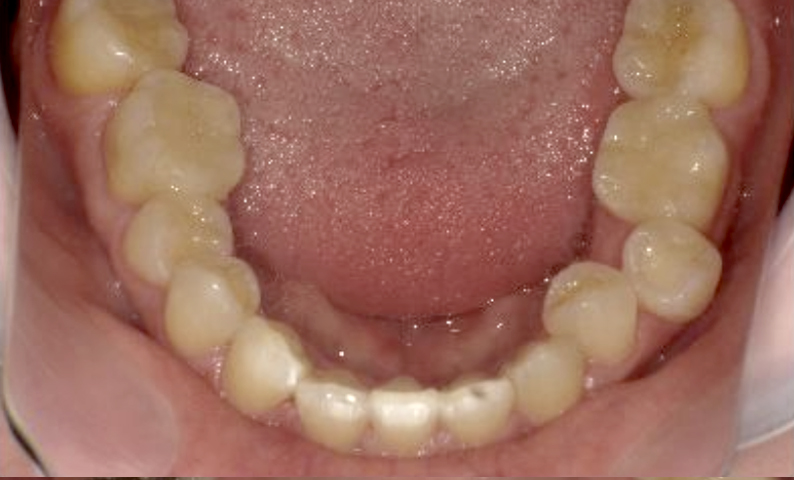

症例_002 上顎だけの部分矯正

治療期間:7ヶ月金額:30万円+税女性前歯のガタガタ上の前歯だけ

| Before | After |

|---|---|

|